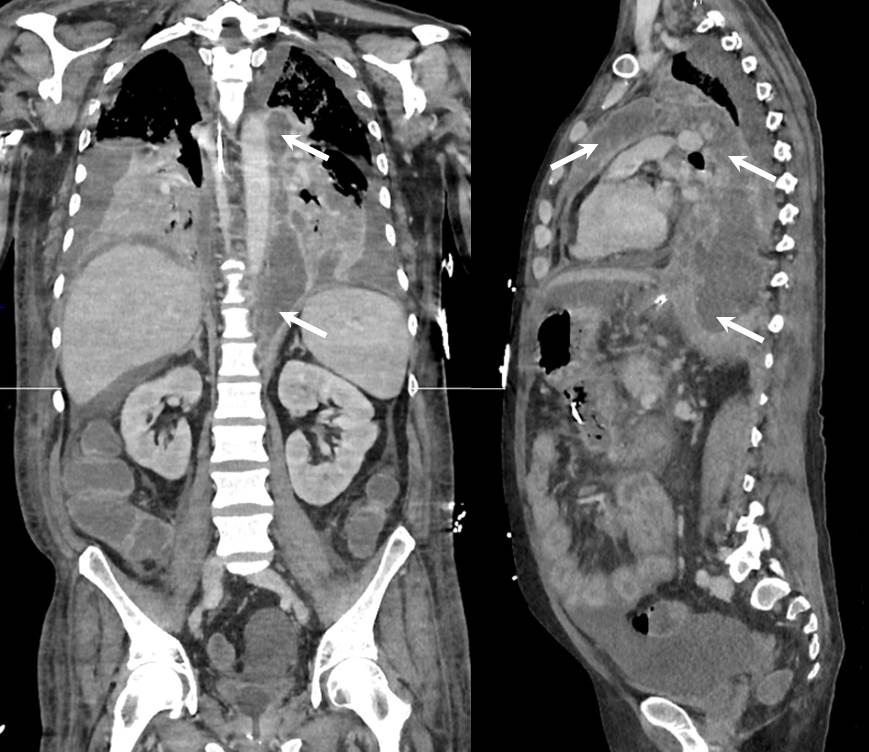

Three weeks after the hospital admission, the patient experienced fever, confusion and respiratory distress requiring mechanical ventilation and intensive care. A new CT-scan revealed bilateral pleural effusion, a non compressive pericardial effusion and a large posterior and anterior mediastinal collection along the left side of aorta spreading from the aortic hiatus to supraaortic vessels (Figure 1, arrows). Blood cultures were positive and grew to Klebsiella spp. A mini-thoracotomy was performed and confirmed the diagnosis of infected mediastinal pancreatic pseudocyst with high level of lipase (49 340 UI/L) and local microbiological samples positive for the same bacteria. Subsequently, the whole mediastinum was washed and drained using a large left thoracotomy.

Figure 1: Chest and abdominal CT-scan in coronal and sagittal views.